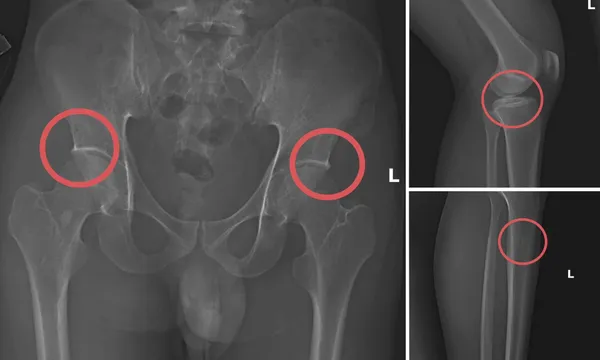

Đáng chú ý, Châu trực tiếp thực hiện hành vi tiêm thuốc mê, rồi dùng kim tiêm, búa, đinh để tác động vào xương người mua bảo hiểm, tạo nên các vết nứt, vỡ xương tương tự tai nạn thật.

Theo Công an tỉnh Phú Thọ, thủ đoạn này vừa tàn nhẫn, vô nhân tính, coi thường sức khỏe, tính mạng của người tham gia, vừa được tính toán kỹ để gây thương tích đúng vị trí có mức chi trả cao, khiến các công ty bảo hiểm khó phát hiện dấu hiệu gian dối.